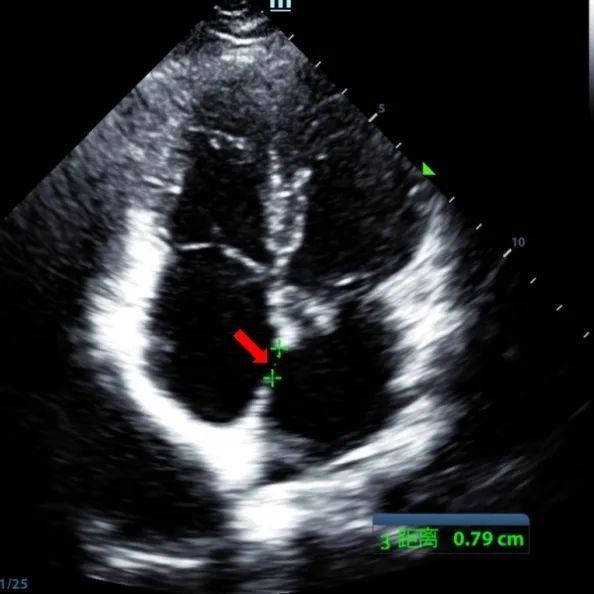

9-летний мужчина с секундовым ASD (7,5-7,9 мм) был обработан с использованием окклюдера MemoSorb BDASD-I 12 мм и системы доставки 12F. Никаких осложнений или сопутствующих заболеваний не было отмечено до процедуры.

Serial echocardiographic follow-ups showed stable device position and favorable cardiac remodeling. Gradual degradation confirmed the occluder's long-term safety and efficacy.